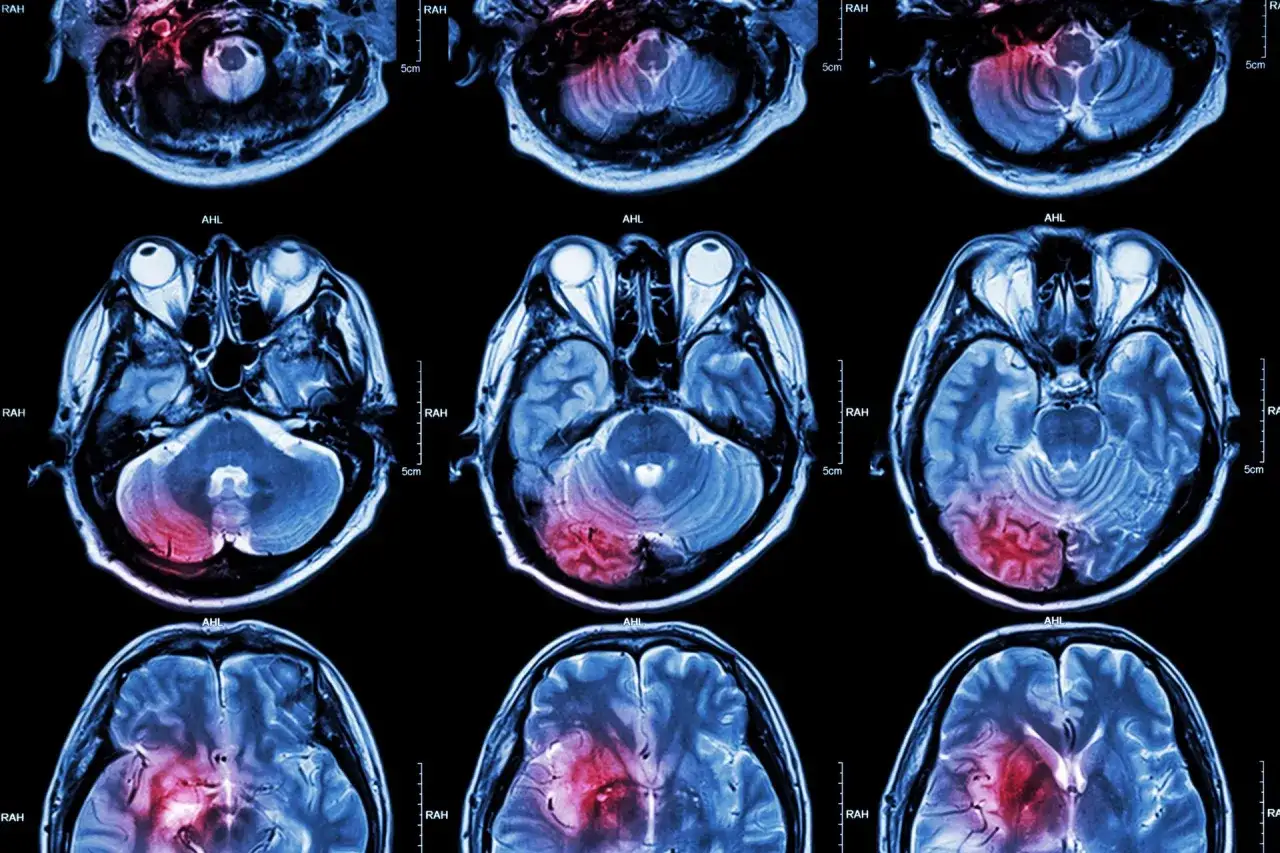

Pierwsze 24-48 godzin po udarze mózgu to czas intensywnej diagnostyki. Lekarze wykonują tomografię komputerową lub rezonans magnetyczny, aby określić rodzaj udaru. To kluczowy moment, od którego zależy dalsze leczenie.